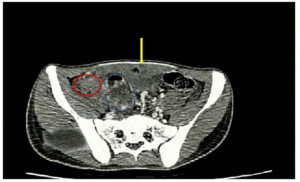

Điều trị bệnh nhân ung thư đại tràng Sigma di căn gan tại Trung tâm Y học hạt nhân và Ung bướu, Bệnh viện Bạch Mai GS.TS. Mai Trọng Khoa, BSCK II Nguyễn Đức Luân, PGS.TS. Phạm Cẩm Phương Trung tâm Y học hạt nhân và Ung bướu, Bệnh viện...